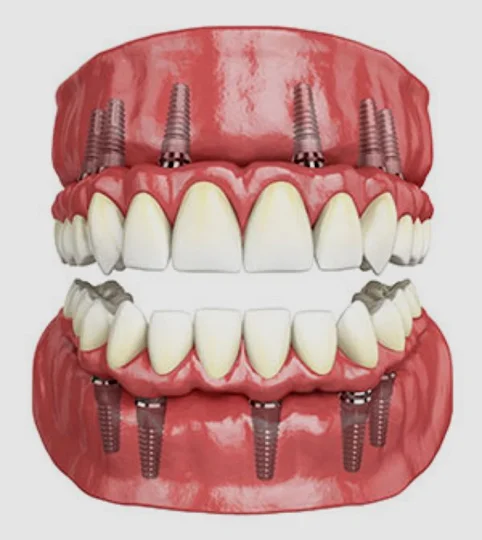

2. Why Crowns Matter After Root Canals

After a root canal:* The tooth loses moisture and becomes brittle

* Chewing pressure can cause cracks

* Bacteria can enter through small cracks

A crown covers the entire tooth, protecting it from these risks. Without a crown, even a beautifully done root canal can fail.

A crown acts like a protective cap, making the tooth strong again.